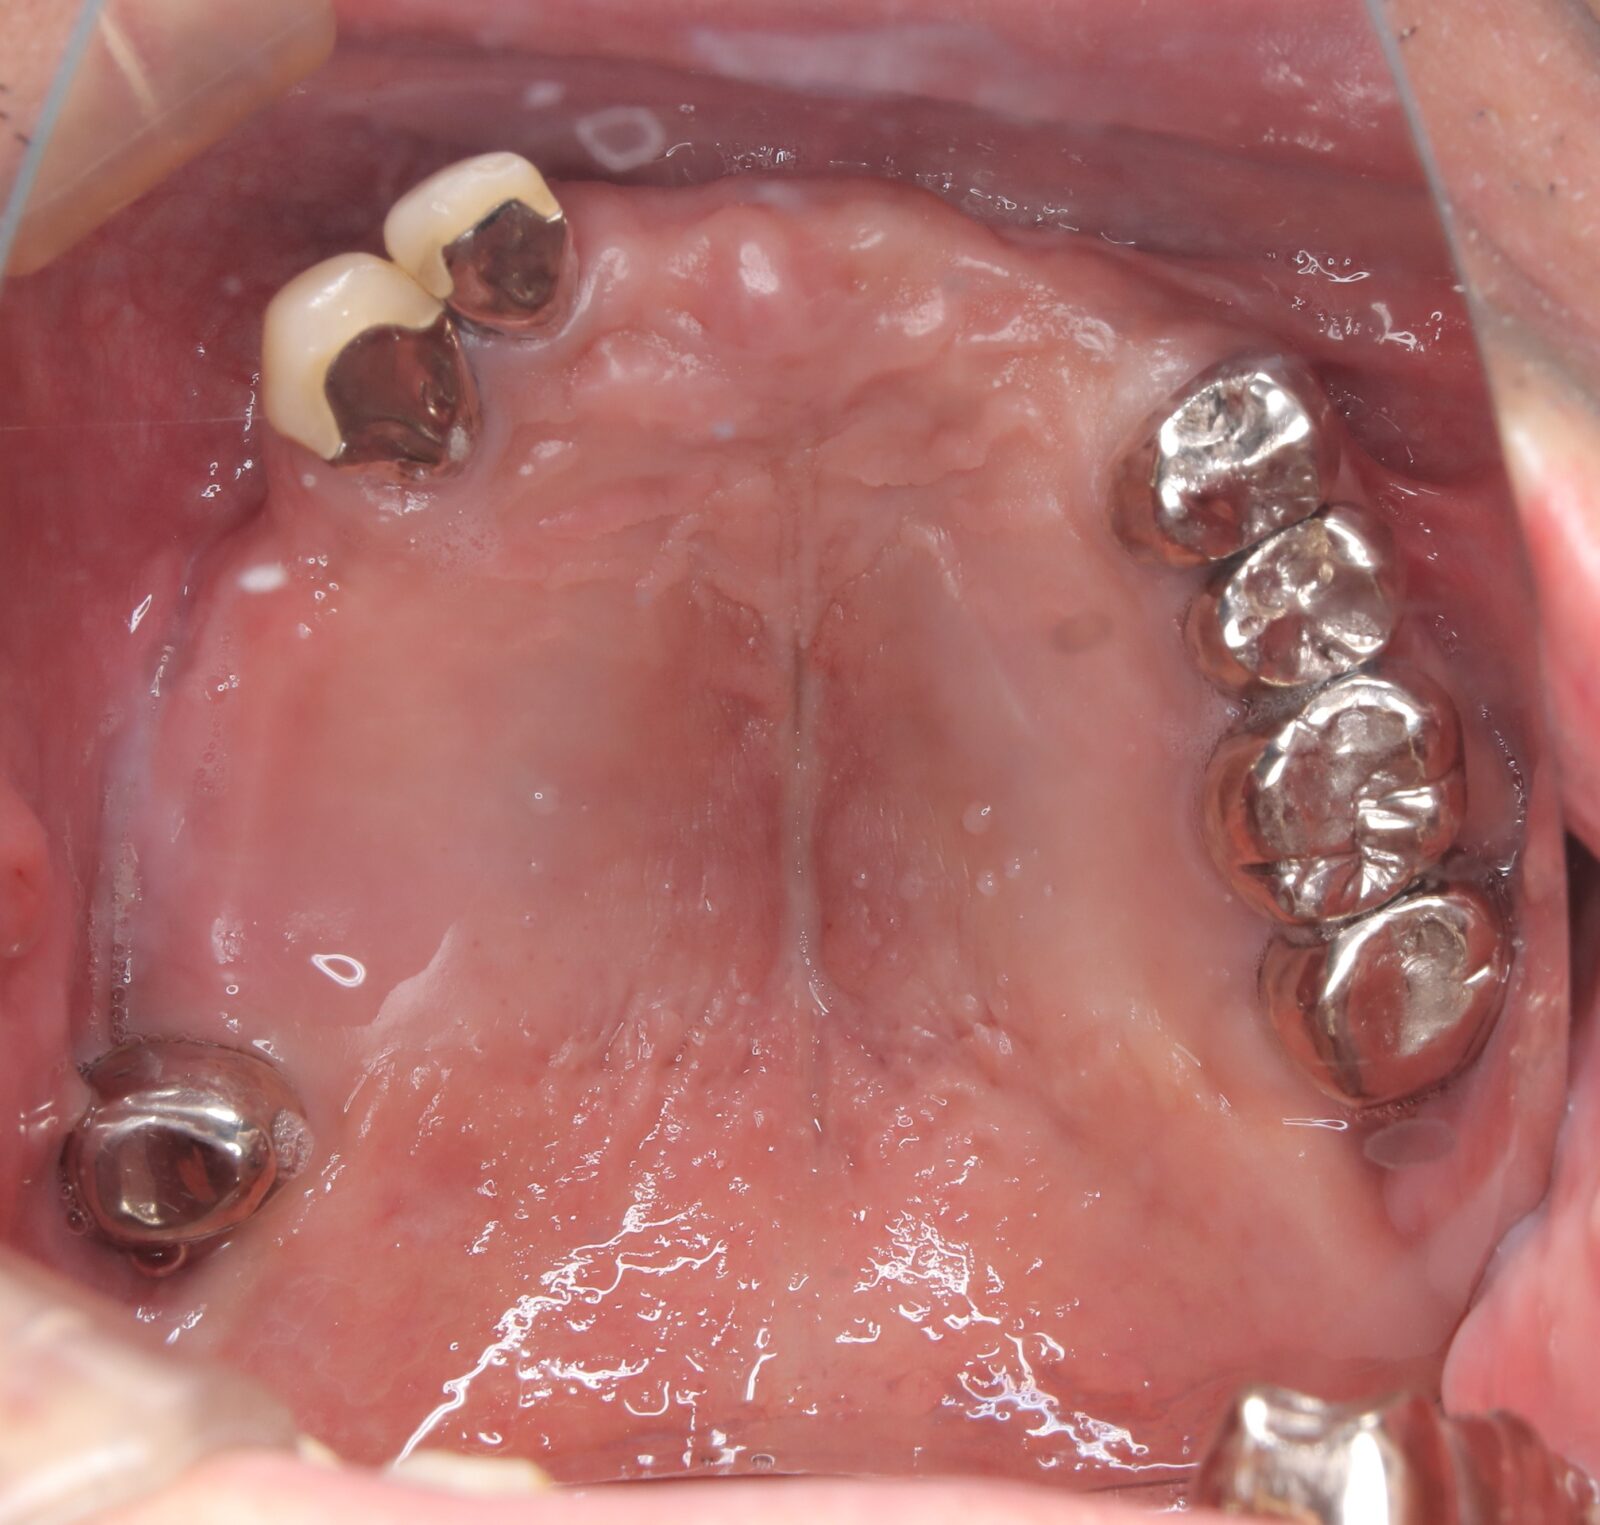

矯正と補綴が必要で実施した症例

左側に隙間。歯の数が少ない。もともと2番と7番がない。(先天欠如)歯の数が少ないため上顎のアーチ全体が小さい。歯槽骨の幅も狭く、歯肉も薄い。骨質も弱かった。

上顎左右2番と6番が先天欠如。下顎左右1番も先天欠如でもともとブリッジが装着されていた。

左右非対称なすきっ歯。上顎の前歯がないので左側の隙間を左右2番相当部に集めた。

上下の前歯が反対の噛み合わせ(受け口)で、干渉しているためうまく閉じることができず、奥歯は左右同時に噛めないので、どこかにずらさないと口を閉じられない。

左右の歯を同時に合わせることができず、どこで噛んだら良いかわからない噛み合わせでした。

小臼歯部は噛み合うことがない側方の開口状態。矯正と補綴が必要なケース。 主訴は顎の不調と歯軋り、夜間の食いしばり。

マルチブラケットとインビザラインを併用し、クラウンとブリッジを装着しました。

上顎左右2番は、歯が入るスペースを作り、ブリッジを装着しました。

他の歯医者で何軒も断られていました。 骨の幅がうすくインプラントはできない。骨の質も柔らかい。PCR検査の結果も歯周病ハイリスク患者でした。

歯の位置は、本人の顎が安定する場所を探して着地した。 左右で噛み合わせが非対称で、理想的な歯のポジションを獲得できなかったものの、左右同時に噛むことができるようになった。

顎関節の症状も落ち着いて、開口障害や、顎の痛みは無くなった。

矯正治療はどの装置を選択しても歯周病のリスクを高めてしまう。

これ以上の歯の移動が歯周病と骨質、骨の代謝のバランスの兼ね合いで困難であると判断し、ここが着地点とした。